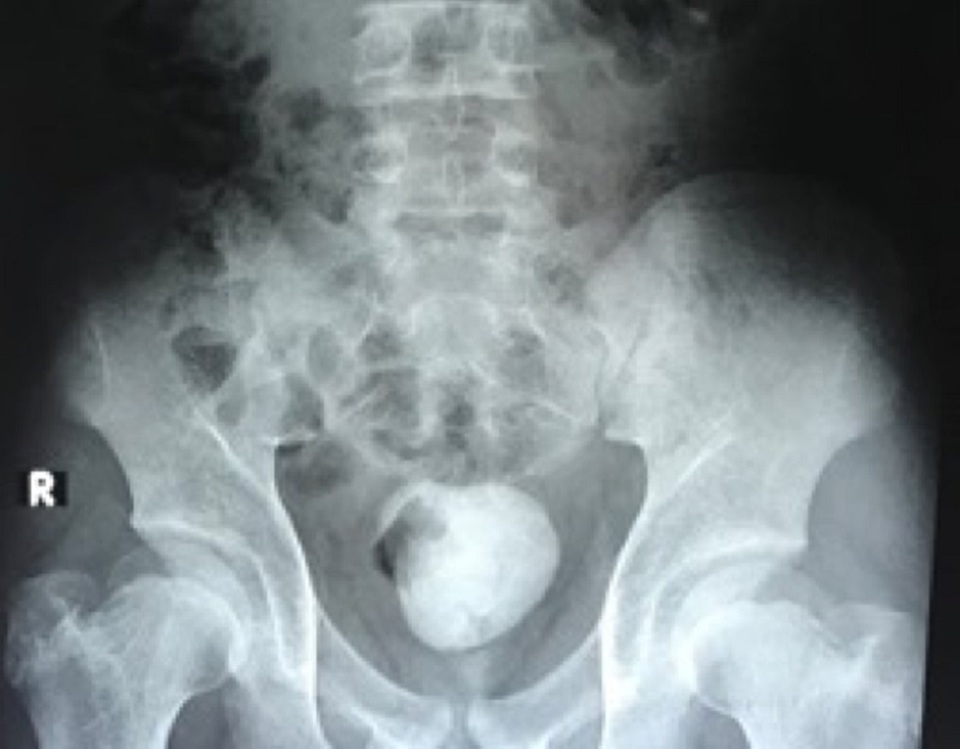

Các xét nghiệm và kết quả khảo sát hình ảnh cho thấy bệnh nhi bị sỏi bàng quang tái phát với kích thước lớn khoảng 10cm. Đây là nguyên nhân khiến cậu bé tiểu khó, tiểu đau, thậm chí gây bí tiểu do sỏi che lấp cổ bàng quang và niệu đạo nên nước tiểu không thoát ra ngoài được. Nước tiểu ứ đọng trong bàng quang tạo điều kiện cho vi trùng phát triển gây nên tình trạng nhiễm trùng đường tiểu.

Bệnh nhi được tiến hành đặt thông tiểu để nước tiểu thoát ra tạm thời và tiêm kháng sinh tĩnh mạch để điều trị nhiễm trùng tiểu. Với đường kính 10cm của viên sỏi, việc tán sỏi bằng laser ít xâm lấn qua ngã niệu đạo – bàng quang hầu như không thể thực hiện được. Do đó phương án mở bàng quang lấy sỏi là lựa chọn duy nhất.